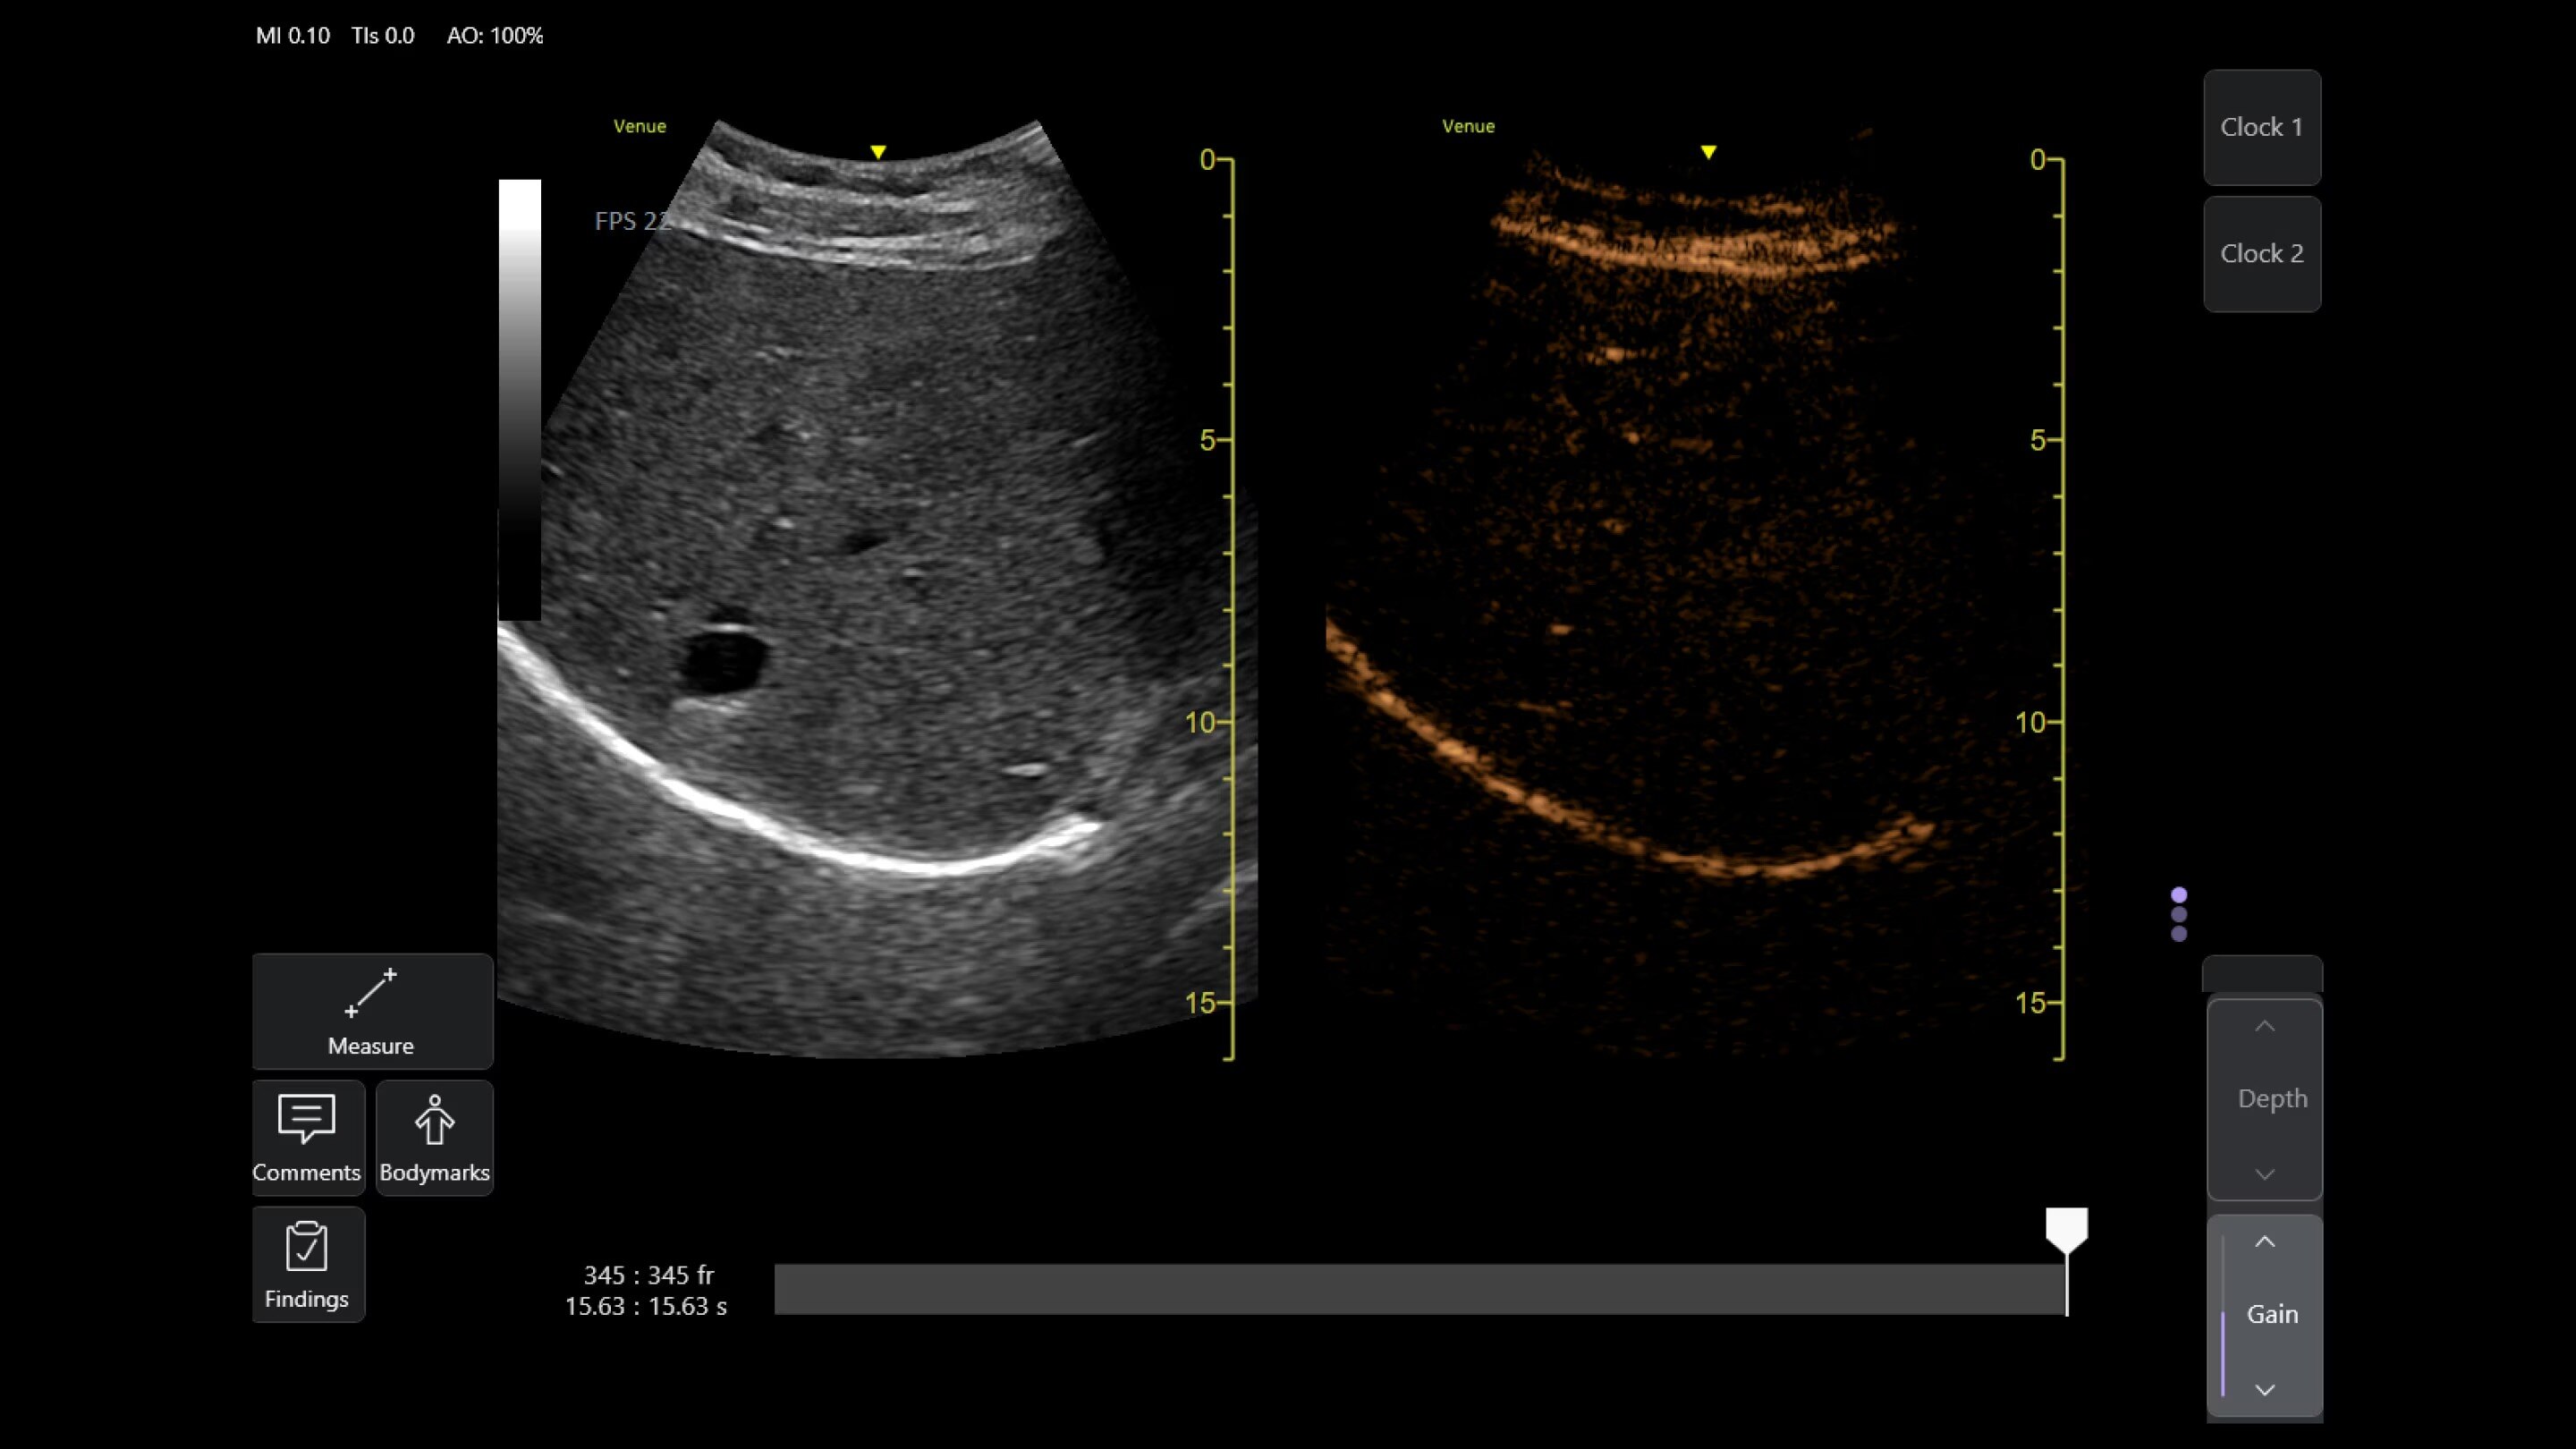

Auto Bladder Volume

Quick and easy measurements

AI-enabled tool provides rapid and easy urinary bladder volume measurements, saving clinicians valuable time and enhancing clinical accuracy. It measures bladder dimensions and calculates the bladder volume from two views: transverse and longitudinal.